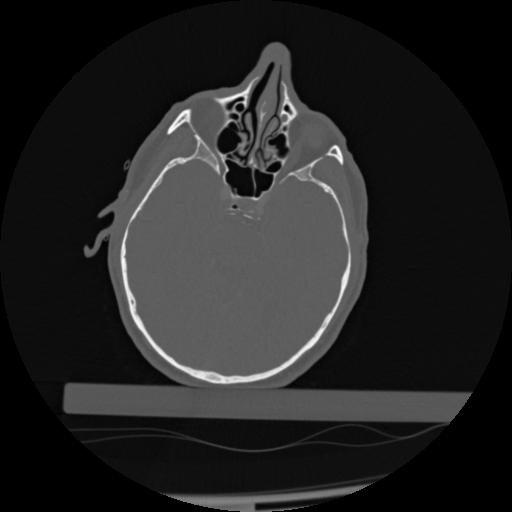

22 ANGIO,CE,Vol,0.5,ANGIO,,